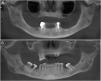

Regarding the imaging aspects of the jawbones in the MM group, solitary or multiple hypodense lesions suggestive of bone involvement were observed in 31 (73.8%) patients. In 28 (83.1%) patients, there were large lesions, with poorly defined margins, with a typical pattern of plasmacytoma. Minor multiple hypodense lesions, exhibiting sclerotic margins, named “punched out” lesions, were observed in the images of 5 (16.1%) patients (Figure 2). Cortical disruption was observed in 7 (22.5%) patients (4 in the upper jaw and 3 in the lower jaw) (Figure 3). The lower jaw was affected in 16 (51.6%) patients and both upper and lower jaws were affected in 15 (48.3%) cases.

Bone hypodense lesions associated with teeth were observed in 33.3% of the CBCT images of MM patients and in 53.6% of controls (p=0.832). Diffuse hyperdense lesions suggestive of florid cemento-osseous dysplasia were observed in 2 (6%) female patients with MM.

Jawbone lesions in MM are commonly mentioned and have been reported as one of the first detected signs of the disease.5,6,8,13–16 Similarly to the results of this study, plasmacytoma lesions6,8 have been described more often than the typical pattern of “punched out” lesions.3,17 Plasmacytoma lesions have been characterized as large and irregular radiolucent lesions, with poorly defined margins.6,8 “Punched out” lesions are commonly visualized as multiple and rounded radiolucencies with no corticalized well-defined margins.3,17 The jawbone lesions are not pathognomonic of MM. Differential diagnosis with other maxillary pathological conditions, such as chronic osteomyelitis, osteonecrosis, osteoradionecrosis, ameloblastoma, osteosarcoma, Paget's disease and other conditions, should be considered in the evaluation of the jaw images.

The majority of MM patients (73.8%) presented jawbone lesions suggestive of MM, as observed in the CBCT images. Other studies have reported smaller frequencies of jawbone lesions, varying from 5.18% to 15.60%.3,8,17 Most of the studies described the imaging aspects of MM mainly in panoramic radiographies,2,6,8,18 while others used intraoral radiographies,2,4,8 computed tomography5 and magnetic resonance imaging.2,5 The high number of jaw bone lesions identified in this study suggests that CBCT is more sensitive than other imaging methods in the detection of myelomatous lesions in the jawbones. The significant correlation between the presence of the bone lesions suggestive of MM in the jaws and other bones suggests that CBCT imaging is a powerful tool in the jaw evaluation of patients with MM. Because of a three-dimensional view of the jawbone, CBCT imaging may show more details, presenting good accuracy, without overlays, and deliver smaller radiation doses than conventional computed tomography. To our knowledge, only one study evaluated the maxillofacial complex of patients with MM using the CBCT as a tool to analyze possible lesions due to multiple myeloma, and found similar results.2